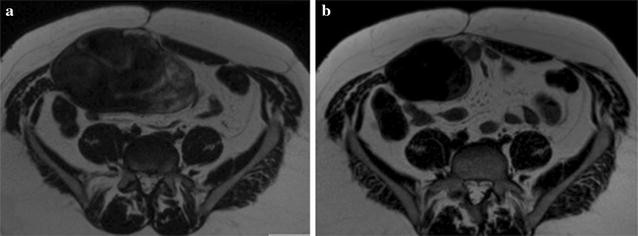

Tamoxifen with or without a NSAID, resulted in symptom improvement in 10 patients (31%)—5 patients on 40 mg tamoxifen, 4 patients on 20 mg tamoxifen and 1 patient on 10 mg tamoxifen (8 of these 10 patients were also taking NSAIDs). Worsening symptoms were experienced by 9 patients (28%)—2 patients on 40 mg tamoxifen, 6 patients on 20 mg tamoxifen and 1 unknown (6 of these 9 patients were also taking NSAIDs). Thirteen patients did not experience any change in symptoms (41%)—9 patients on 40 mg tamoxifen, 4 patients on 20 mg tamoxifen (10 of these 13 patients were also taking NSAIDs). The majority of patients with symptomatic benefit did not have significant changes in size or signal on MRI (Fig. 1a, b).